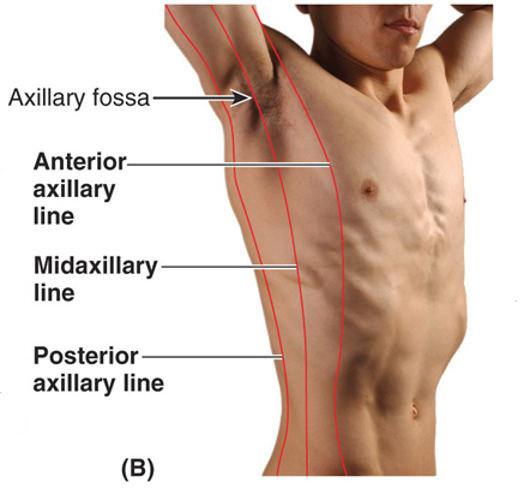

name the 3 lateral vertical lines and describe them?

which one is formed by the pec major?

which one goes right through the armpit?

which one is formed by the latissimus dorsi and teres major?

Anterior axillary line...vertical line along anterior axillary fold (formed by pec major)

Mid axillary line...vertical line though apex of axilla (armpit)

Posterior axillary line...vertical line through posterior axillary fold (formed by latissimus dorsi and teres major)